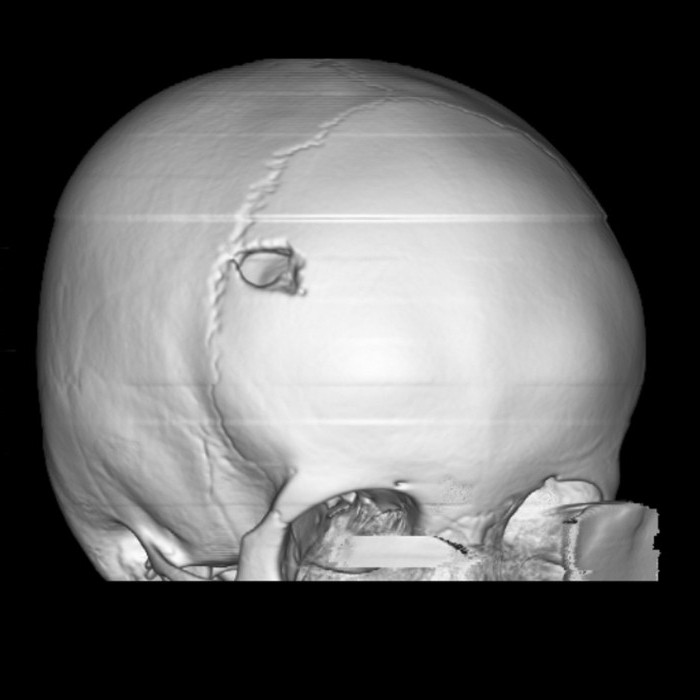

Рисунок 1. 3D-реконструкция костей черепа с солитарной эозинофильной гранулемой

https://radiopaedia.org/cases/eosinophilic-granuloma-skull